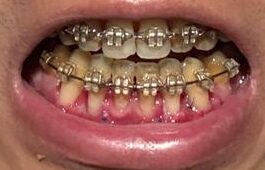

左(上)から:術後5時間後、術後17時間後、術後1週間後、術後3週間後

左(上)から:術後3時間後、術後19時間後、34時間後、58時間後、65時間後、89時間後、114時間後、154時間後

・2026年2月21日撮影

・2025年9月13日撮影

・2022年10月1日撮影(約3年前)